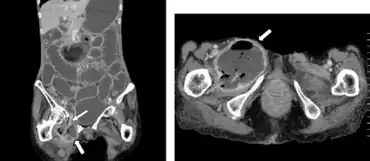

| Computed tomography revealed a right obturator hernia arrow and abscess spreading to right thigh | |